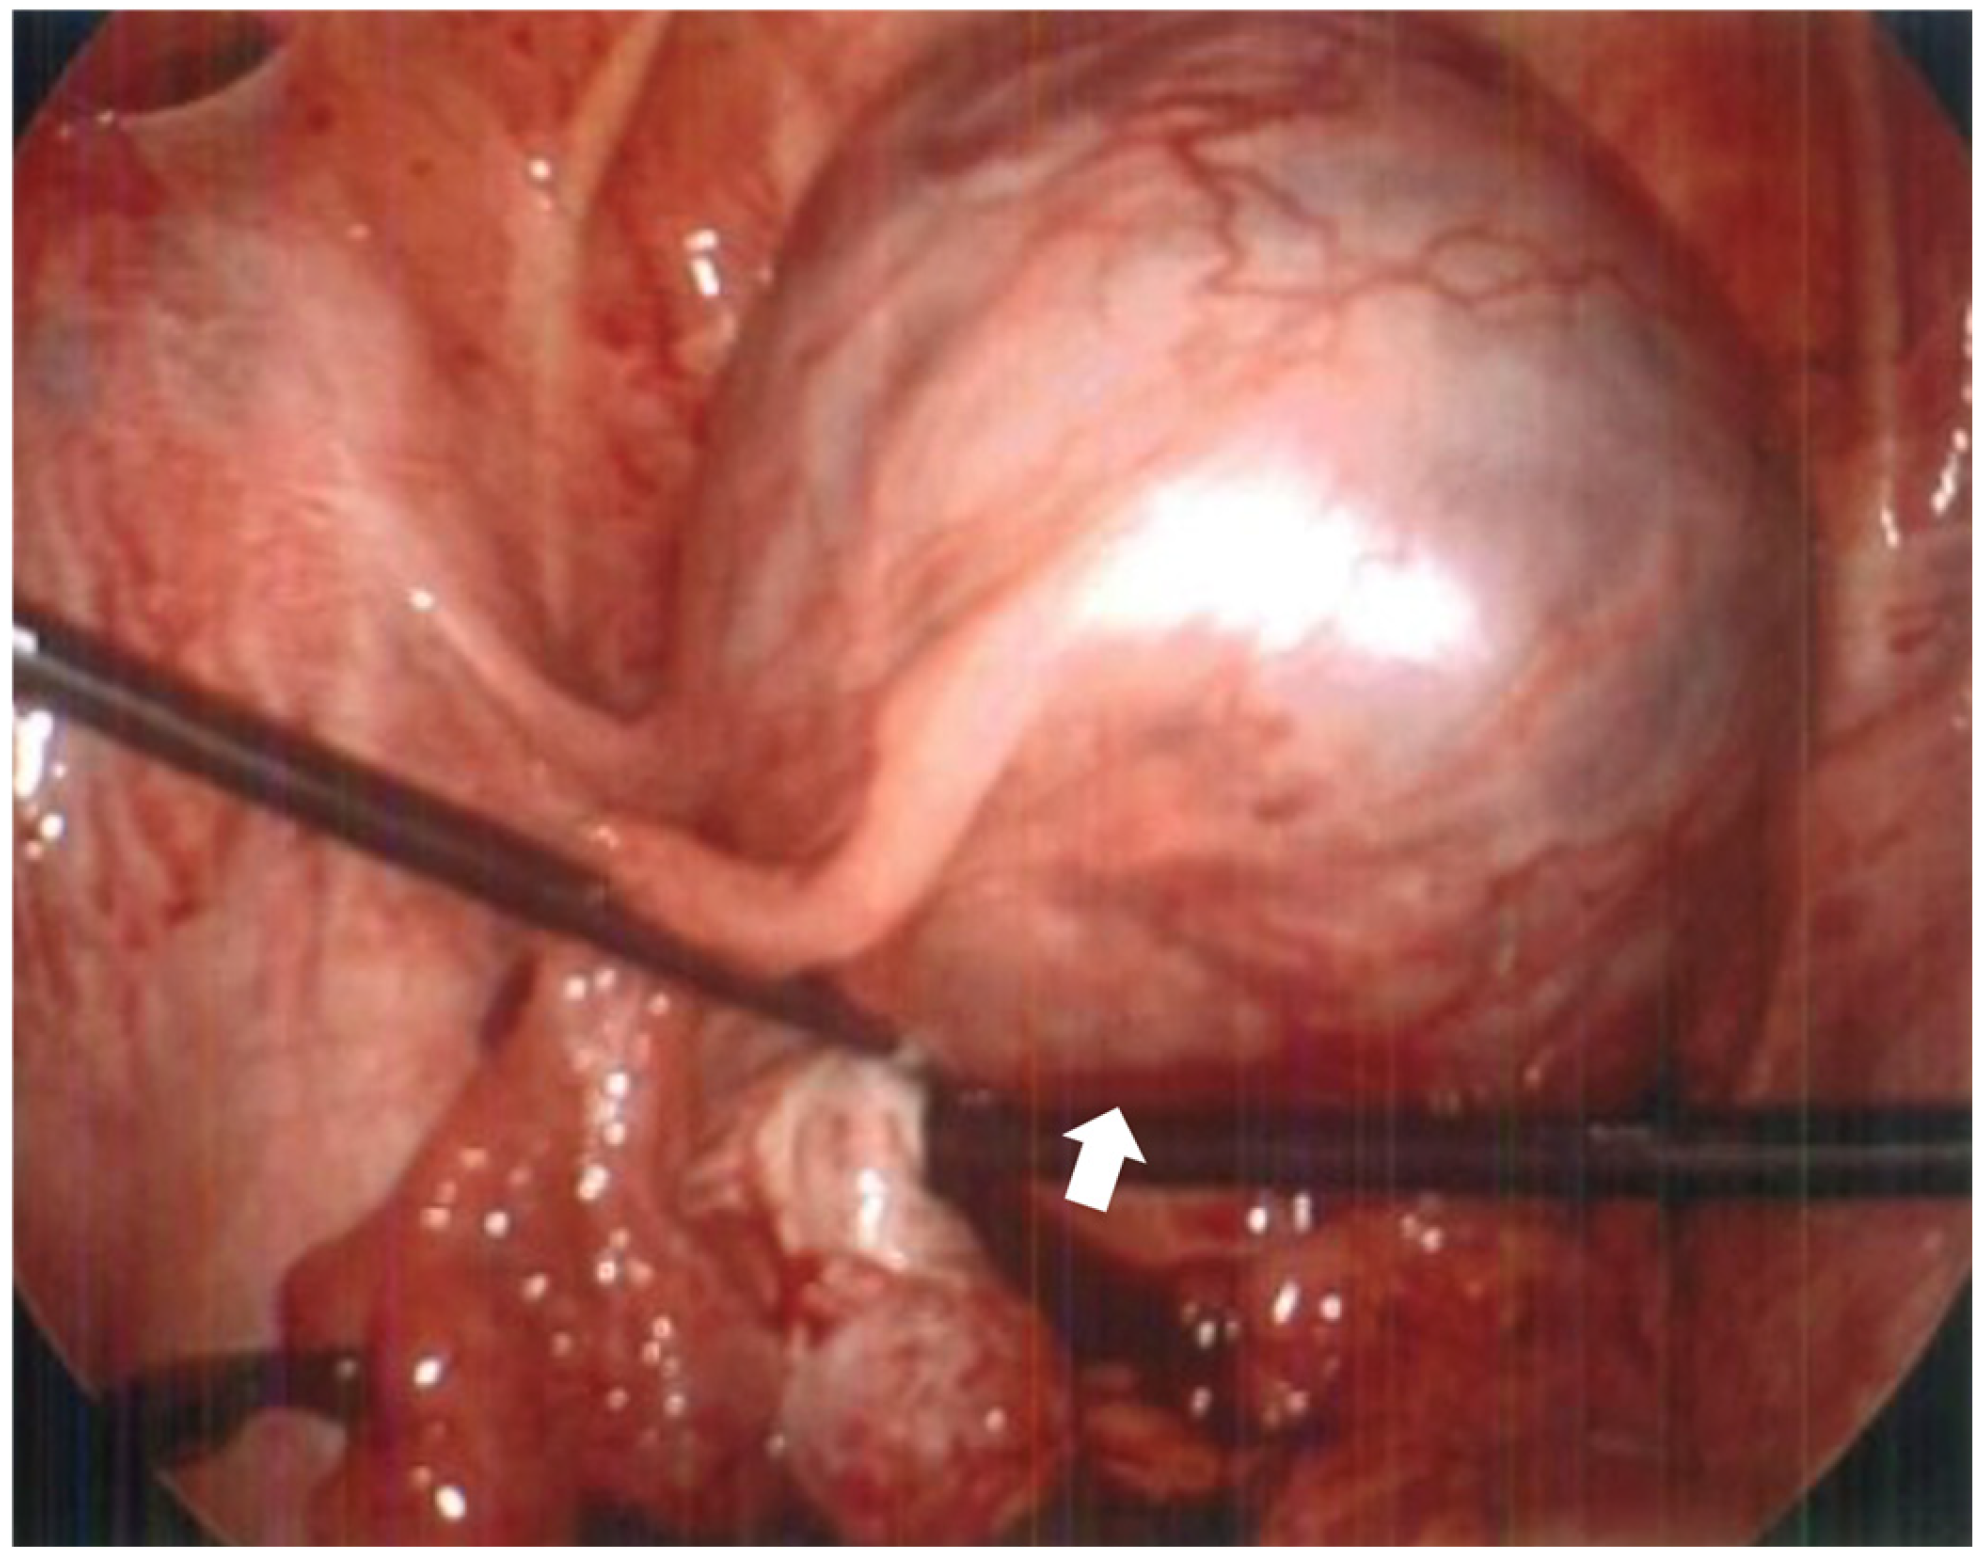

Figure 2.

MRI without contrast showed that the ectopic gestational sac exerted mass effect upon the uterus and bladder, and was associated with a moderate amount of pelvic fluid. (a) Axial T2 HASTE demonstrating ectopic pregnancy in the left adnexa with associated mass effect on the bladder and uterus which deviate to the right. The placenta is located anteriorly within the gestational sac. (b) Sagittal T2 HASTE demonstrating ectopic pregnancy located anterior to uterine fundus and superior to bladder. The anterior wall of the gestational sac is located approximately 1.3 cm deep to the overlying skin surface. There is a moderate amount of complex free pelvic fluid. (c) Coronal T2 HASTE demonstrating intact gestational sac superior to the bladder in the left adnexa. The left ovary is partially visualized superior to the gestational sac and contains an incidental 2.0 cm follicle.